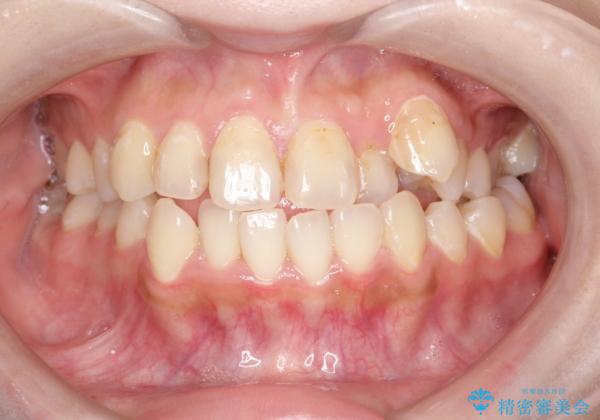

八重歯をインビザラインで非抜歯矯正

- 八重歯を主訴に来院されました。

インビザラインにて奥歯を後方に移動して八重歯が入るスペースを確保してく矯正する計画としました。

八重歯と前歯のガタガタがなくなり、歯並びがきれいになったのと、かみ合わせも改善することができました。